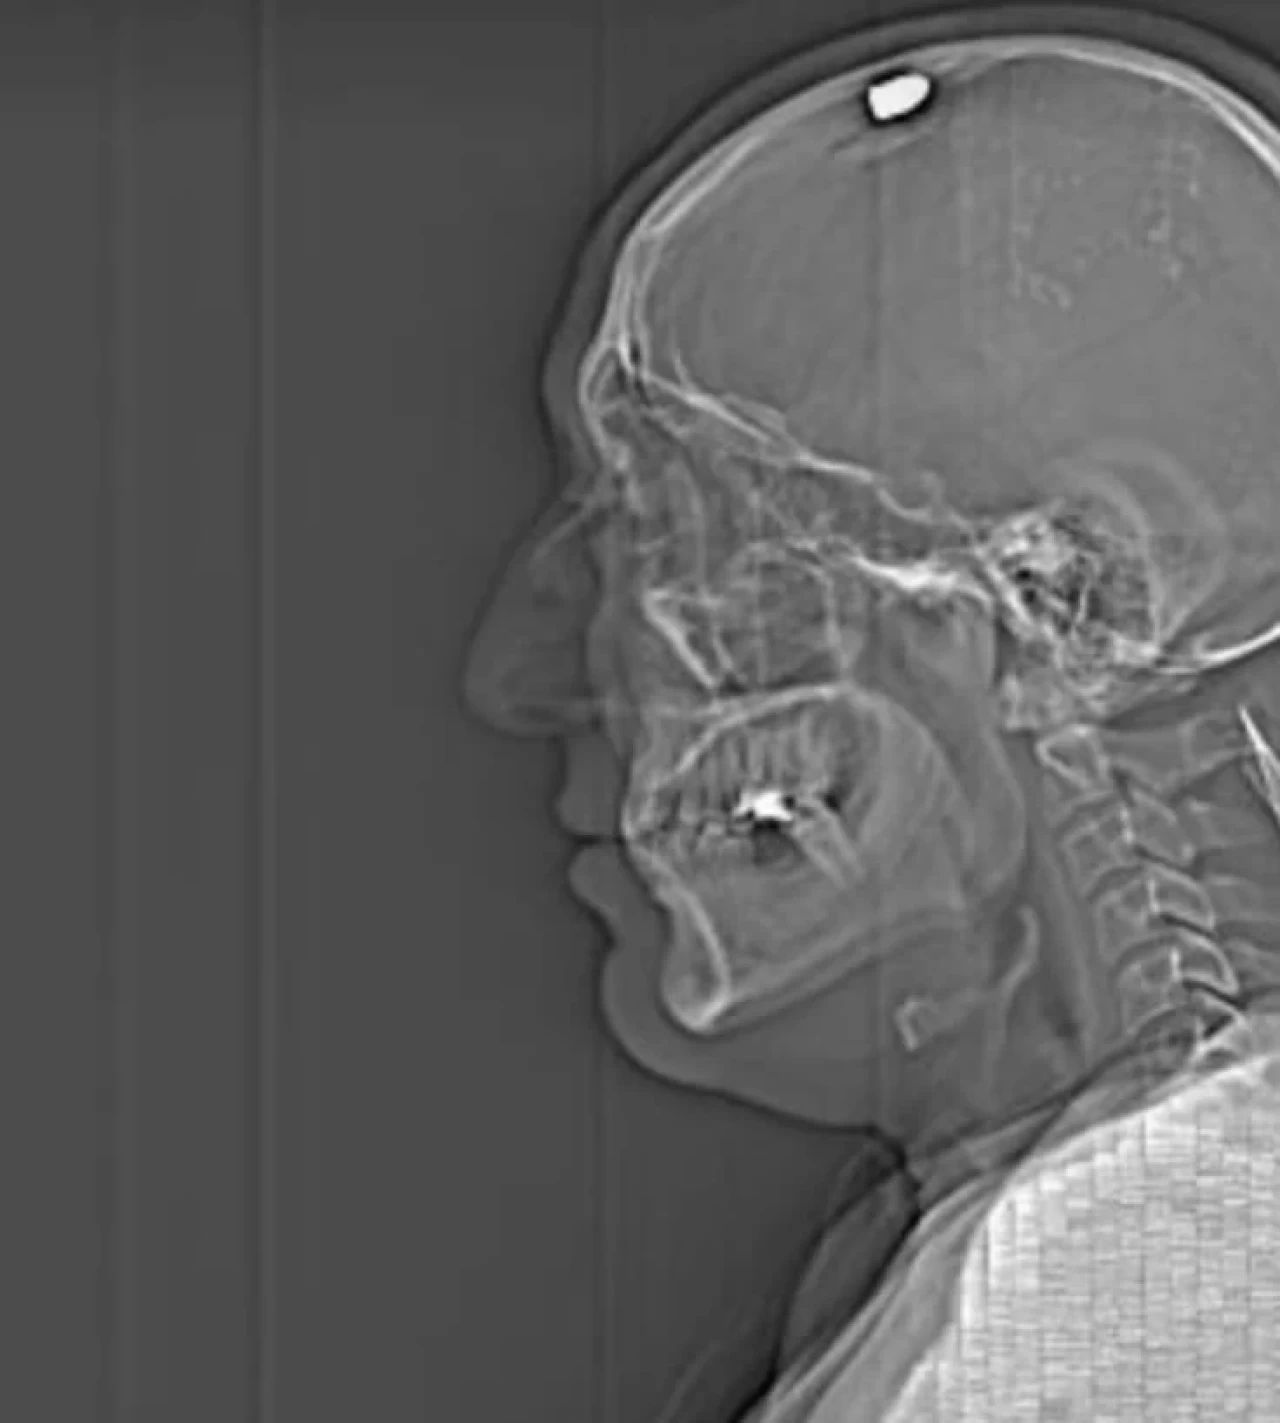

Başına kurşun isabet eden Savaş Koç, saldırı anında ölü taklidi yaparak saldırganlardan kurtulduğunu belirtti. Olay sonrası hastaneye kaldırılan Koç, bir aylık tedavi ve ameliyatların ardından taburcu oldu. Saldırının ardından sağlık sorunları yaşayan Koç, sorumluların cezalandırılmasını istedi.